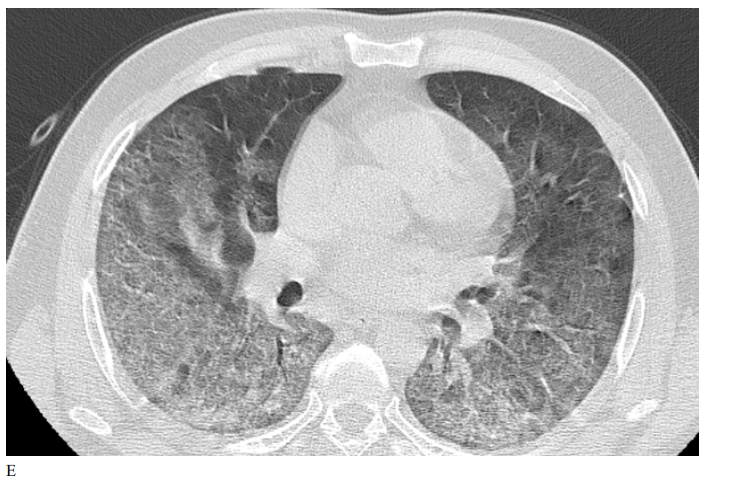

Figure 3: Male patient in NRIZ group shows diffuse bilateral ground glass opacities with alveolar infiltration mainly lower lobes, Covid severity score 12; while figure E After 03 months treatment shows marked resolutions of pervious bilateral pulmonary ground glass opacities and alveolar infiltrates, Covid severity score 6.